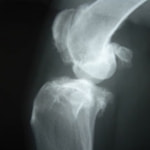

- ■X線

- レントゲン写真により、骨、関節または周囲軟部組織の構造を評価します。